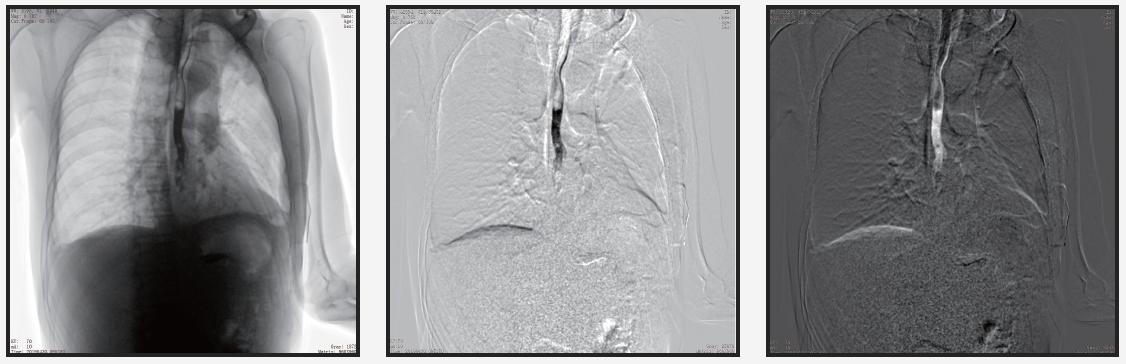

自主研發(fā)的組織均衡技術(shù)

人體圖像通過組織均衡后,圖像細(xì)節(jié)更突出,肺紋理末端細(xì)小血管及骨骼的紋理、肌肉層次等均可清晰顯示。

專業(yè)級圖像采集卡

采用新型降噪、邊緣增強(qiáng)濾波、對比度增強(qiáng)等實時處理技術(shù),使圖像處理速度更快、圖像質(zhì)量更好。